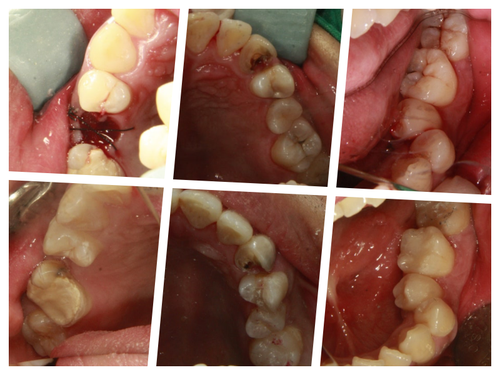

발치가 필요한 치아 치료는 미루시고 나머치 충치 치료를 진행.. 인레이 인상뜰 때 주무시면서 구토까지 하셨다.. 옆에서 이 모든과정을 도와준 우리 직원이 글을 쓰면서 다시 한 번 고맙다..

그래도 무사히 계획된 치료를 다 받고 치료 후 사진도 수면 상태에서 겨우 찍어서 환자분께 보여드렸다..

어시스트와 정말 힘든환자였다며, 우리가 아니면 누가 치료해드릴 수 있었겠냐며 ,몇 번 치료하면서 이환자에 대한 노하우가 생기지 않았냐며, 웃으며 힘든 시간들을 서로 위로해본다..